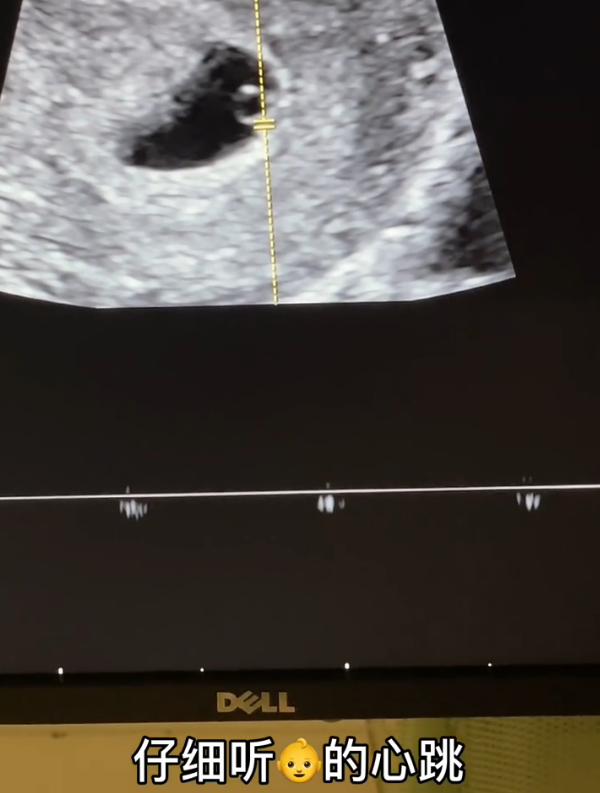

Piggy gentleman accompanied bag yesterday go doing produce check, bask in the B that gave the child to exceed, still share the heartbeat of darling together with everybody. Although small make up and did not hear what voice, but what still can feel piggy is excited, when he is together with Han Anran at that time, can do not have so on the heart passes.

Bag the deep feeling that hears piggy gentleman professions, on the home on the side the palpitant reputation that still has the child, immediately excited to wept. This to a woman, it is very happy hour absolutely, she should become a mother immediately, and still have the boy friend that loves her so.